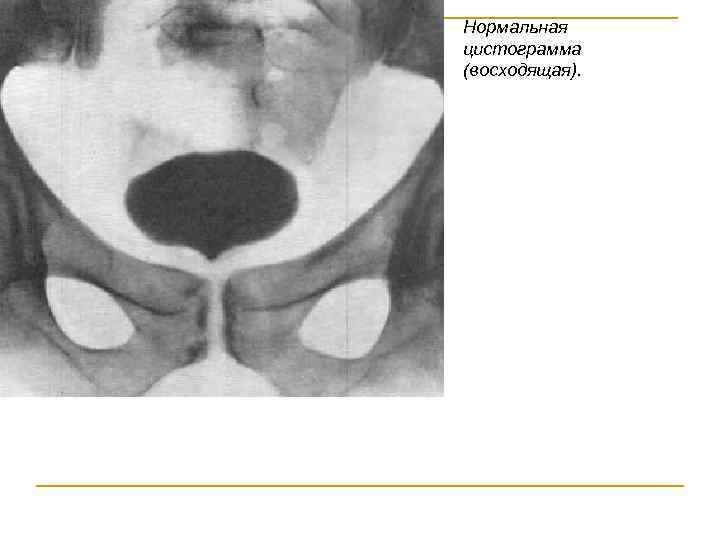

ЦИСТОГРАФИЯ метод исследования мочевого пузыря путем предварительного наполнения его газообразным или жидким контрастным веществом с последующей рентгенографией. Цистография позволяет получить наглядное представление о контурах его полости. Для цистографии используют жидкие и газообразные контрастные вещества. Применение воздуха и масляных растворов в качестве контрастных веществ недопустимо ввиду возможности эмболии. Цистография может быть нисходящей (экскреторной) и восходящей (ретроградной)

Нормальная цистограмма (восходящая).